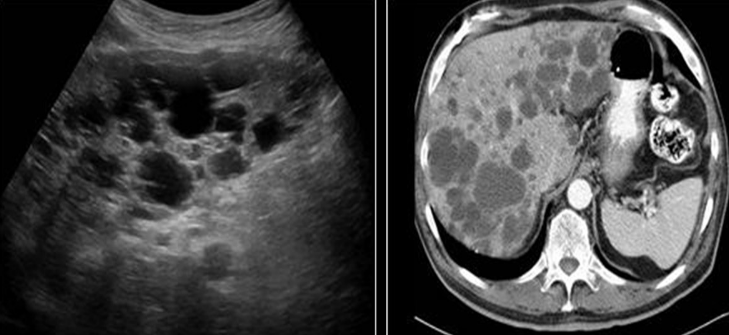

Identify this image.

Biliary hamartoma or von Meyenburg Complexes